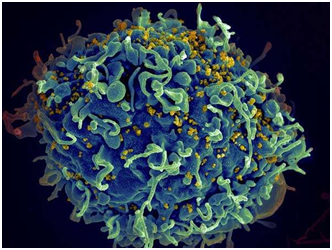

HIV通过破坏人体的T淋巴细胞,进而阻断细胞免疫和体液免疫过程,导致免疫系统瘫痪,从而致使各种疾病在人体内蔓延,最终导致艾滋病。由于HIV的变异极其迅速,难以生产特异性疫苗,至今无有效治疗方法,对人类健康造成极大威胁。

6.Sci Rep:重磅发现!感染细胞所释放的细胞颗粒或能促进HIV感染的扩散

据美国国家卫生研究院的研究人员的研究显示,艾滋病毒似乎征服了感染细胞释放的纳米级结构,以感染新细胞。被称为细胞外囊泡(EVs),这些气泡状结构由许多种类的细胞组成,并且在大多数情况下被认为能将分子从一个细胞转移到另一个细胞,从而提供通信手段。 NIH科学家发现感染艾滋病毒的细胞似乎产生了EVs,其操纵前瞻性宿主细胞将感染传递到其他细胞。该研究出现在科学报告中。

当被细胞释放时,EVs和HIV都携带细胞膜中发现的许多蛋白质,Margolis博士解释说。然而,EV携带CD45蛋白和乙酰胆碱酯酶,而HIV则不携带。使用针对这些蛋白质的抗体,研究人员能够将EV从艾滋病毒的实验室准备工作中剔除。他们发现艾滋病毒感染细胞产生的EVs也在其表面上携带有HIV蛋白质,gp120,HIV在感染过程中与细胞结合。

研究人员将EV-缺乏的样本添加到人类淋巴组织块时,与保留EVs的对照样本相比,培养物中的HIV感染率下降了55%。研究人员认为, gp120的损失(如果没有从艾滋病毒中移除,EVs将能够提供gp120)会导致艾滋病毒感染的下降。虽然EVs缺乏感染细胞的艾滋病毒RNA,研究人员认为,EV表面上的gp120可以与宿主细胞相互作用,使艾滋病毒更容易感染。